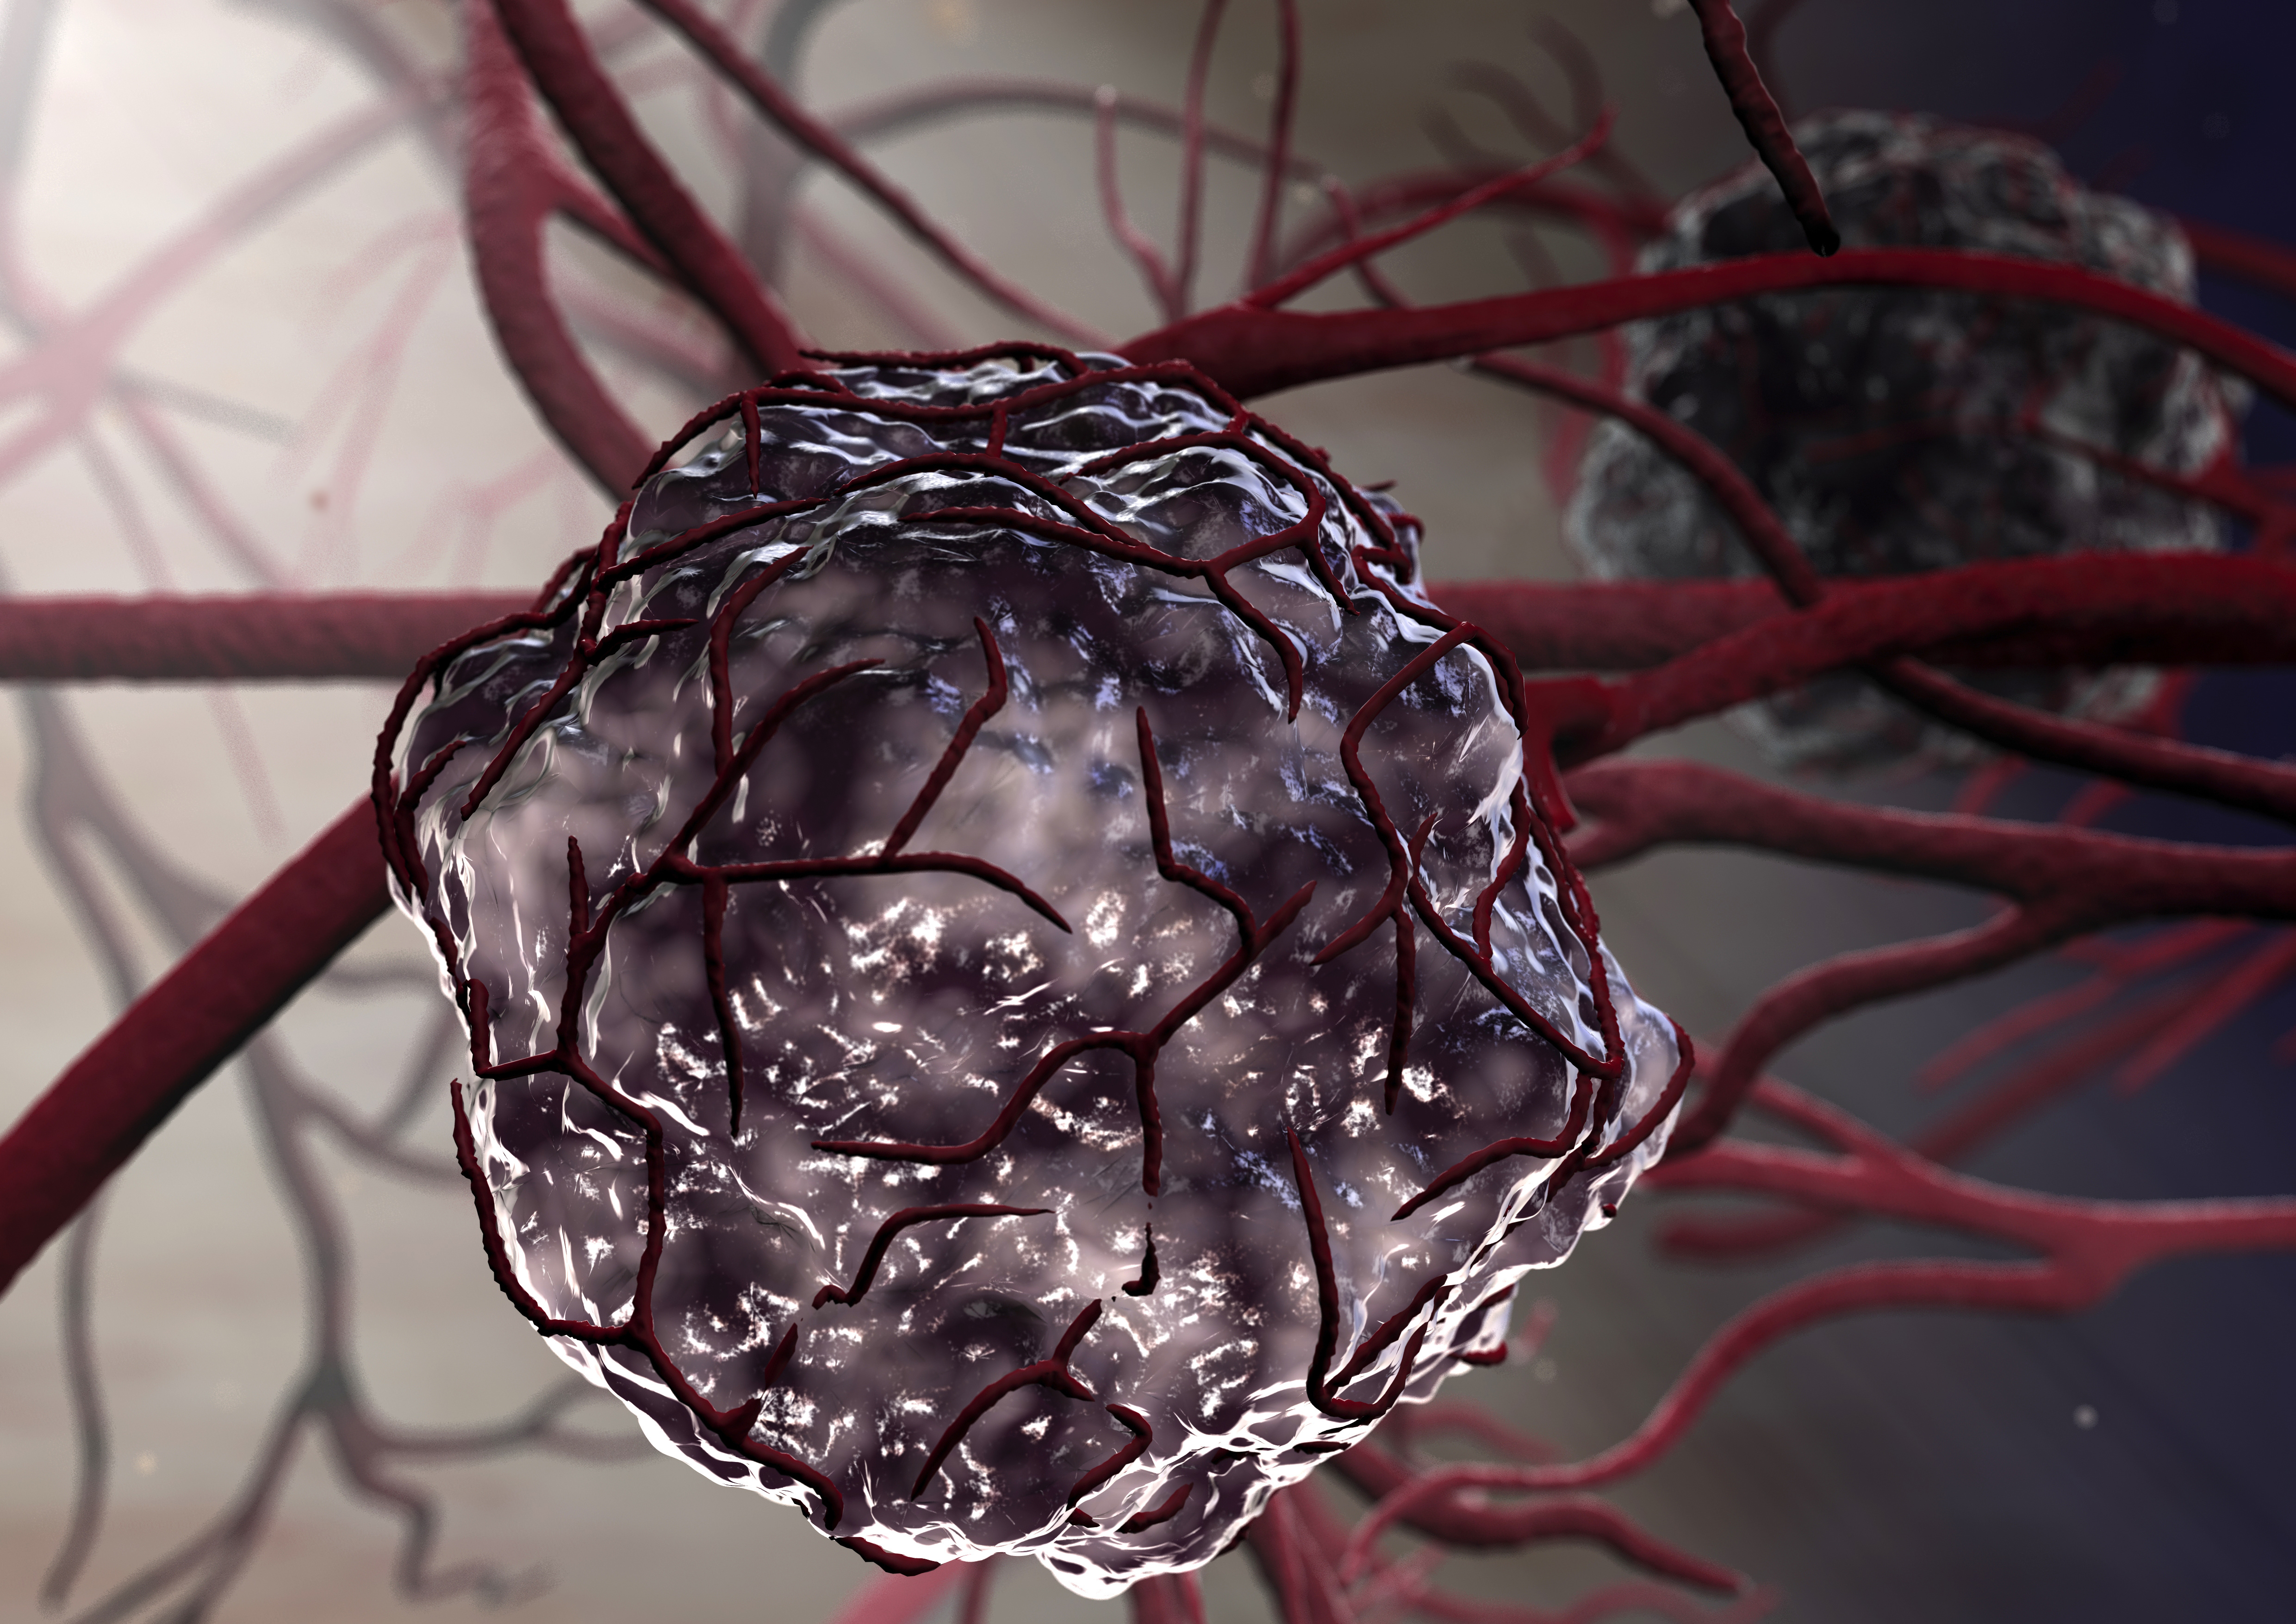

Раковая шишка – это заболевание, которое поражает кожу и слизистые оболочки. Она может возникнуть в различных частях тела и иметь различные внешние проявления. В данной статье мы представляем вам многочисленные фотографии раковых шишек, чтобы вы могли узнать, как они выглядят.

Фото раковой шишки на теле

Раковые шишки могут возникать не только на лице, но и на других частях тела. На фотографиях вы можете увидеть примеры раковых шишек на шее, руках, ногах и туловище. Обратите внимание на различные формы и размеры раковых шишек, а также на их внешний вид.